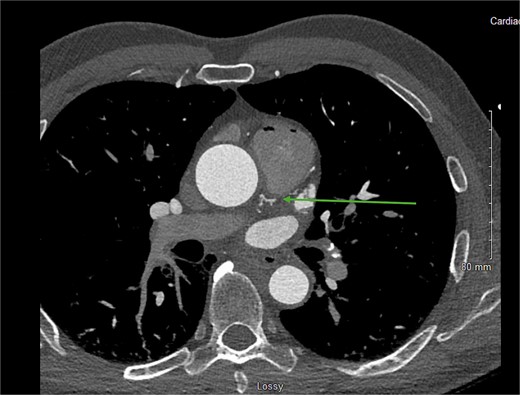

The CCTA revealed a well-developed CPF originating from the proximal LAD (Fig. 1), with moderate stenosis (50–70%) in the proximal LAD. The patient’s total coronary artery calcium score (Agatston score) was 672, indicative of advanced coronary atherosclerosis. Coronary angiography confirmed a diffuse 60% stenosis in the ostial and mid LAD, with mild luminal irregularities (<20%) in the left main coronary artery and right coronary artery (RCA). It also redemonstrated the presence of proximal LAD to pulmonary artery fistula (Fig. 2). No significant oxygen saturation step-up was observed, indicating the absence of a hemodynamically significant shunt.

CCTA showing the CPF originating from the proximal LAD (green arrow).